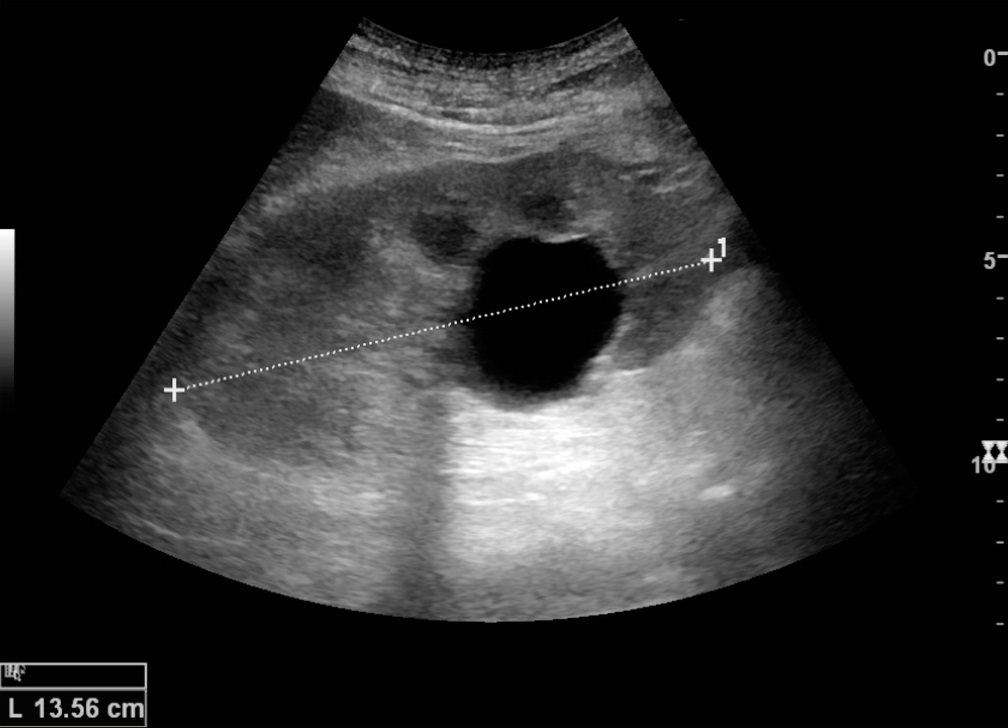

УЗИ позволяет оценить размеры почек, их расположение, структуру и наличие каких-либо изменений. Если была киста почки на УЗИ обнаружена, врач фиксирует её размеры (длину, ширину, глубину), изучает содержимое и определяет, насколько она влияет на функции почки.

Размер кисты играет важную роль в оценке её значимости. Кисты размером до 1 см редко вызывают какие-либо симптомы. Однако если образование превышает 5 см, оно может сдавливать ткани почки, нарушать кровообращение или затруднять отток мочи. В таких случаях врач может порекомендовать дополнительные обследования, например, КТ или магнитно-резонансную томографию МРТ, чтобы детально изучить её структуру.